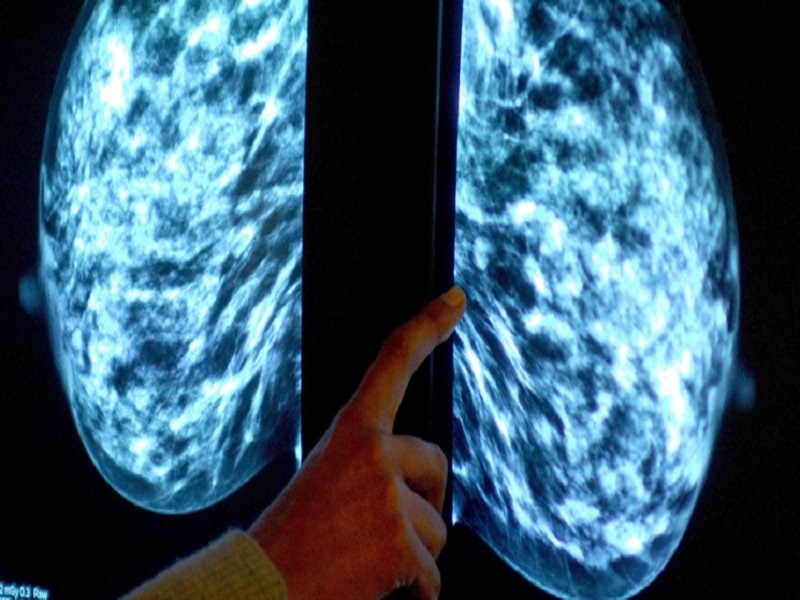

وی افزود: در نظام بهداشتی فعلا سه سرطان سینه و سرطان دهانه رحم در خانمها و همچنین سرطان روده بزرگ هم در زنان و مردان در حال غربالگری است.

شاهآبادی گفت: زنان ۳۰ تا ۶۰ سال برای غربالگری سرطان سینه و سرطان دهانه رحم میتوانند به نزدیکترین پایگاه بهداشتی محل زندگی در شهرها و خانههای بهداشت در روستاها مراجعه کنند و اگر مشکوک به سرطان باشند به سطح 2 درمان برای ارائه خدمات تخصصی ارجاع داده میشوند.

وی گفت: در طول این طرح تاکنون ۲۰۹ مورد سرطان سینه و ۷۱ مورد سرطان روده بزرگ در مراحل اولیه تشخیص داده شده است. خیلی از سرطانها اگر به موقع تشخیص داده شود، درمان میشود.